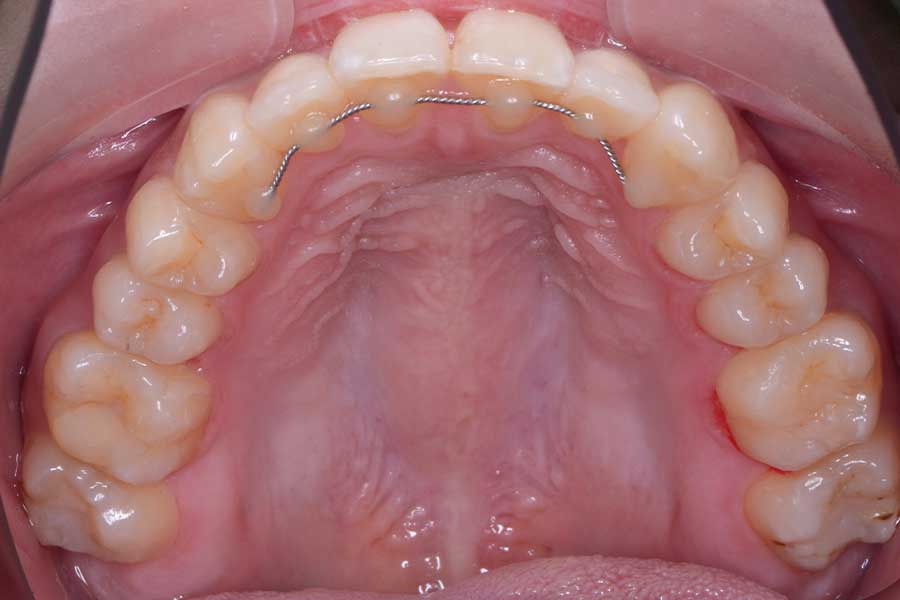

治療後

主訴 前歯で咬み切れるようになりたい

治療内容 ハーフリンガル矯正(上顎裏側・下顎表側矯正)